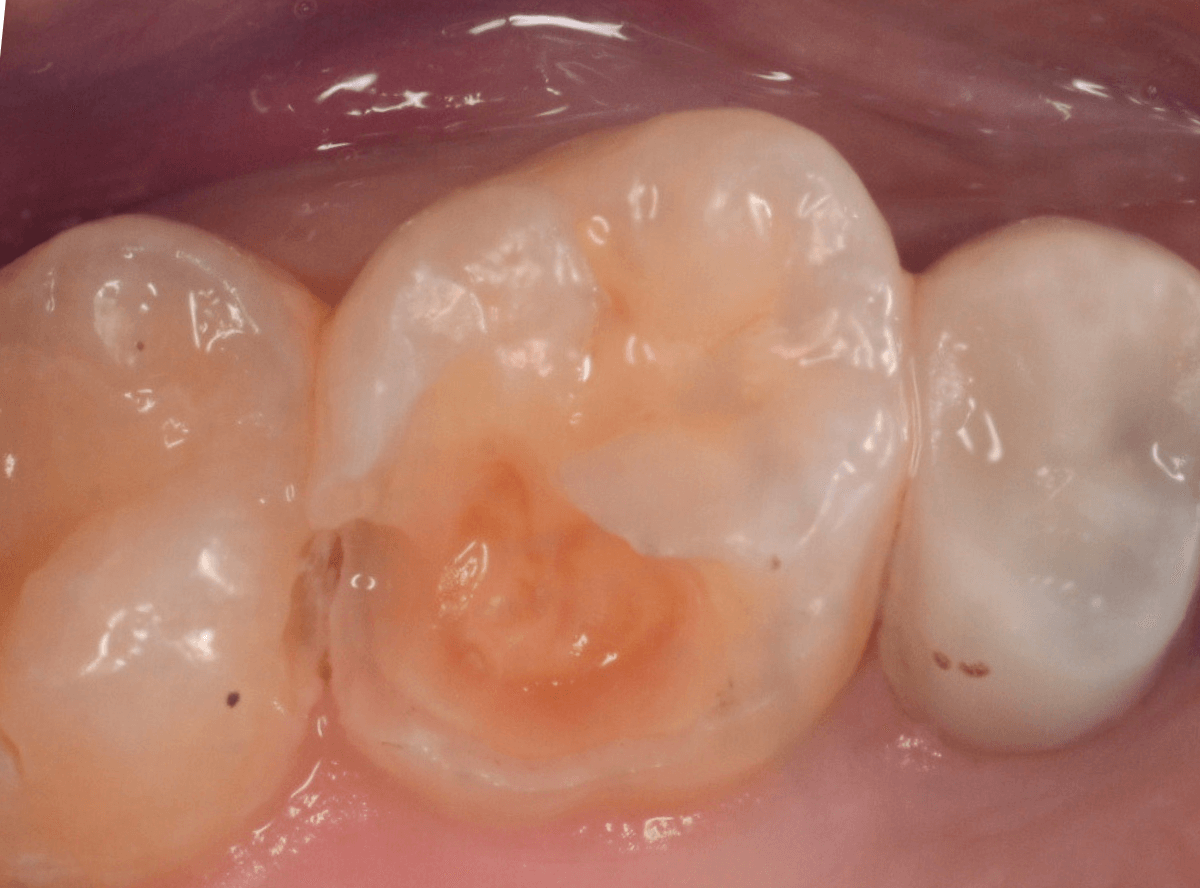

Case.20 劣化したレジン側面から進行した虫歯

「つめものが欠けたまま長期間放置して、歯がしみる」という訴えで来院された患者さんさんです。

拝見すると、劣化したレジンが欠けて、中で虫歯になっているのがわかります。

レジンを外しながら、虫歯を確認します。

慎重にレジンを除去しましたが、途中で露髄(神経が露出する事)しました。

歯の神経の中には、血管も含まれているので、神経が露出すると、このように出血します。

「しみる、痛い」などの明確な強い症状がある場合、このような状況の事が多いです。

今回は出血量が多く、神経を除去する治療(抜髄)の可能性が高いとも感じましたが、できる限り神経を保存する方法を取ることにしました。

神経を保護するお薬をつめて蓋をしてしばらく経過観察します。

神経を除去すると、治療期間が長引くうえに、歯の寿命がとても短くなってしまいます。

できるだけ歯の神経を残すためには、症状が出てからの歯科受診ではなく、定期的なメンテンナンス受診を続けるようにしてください。